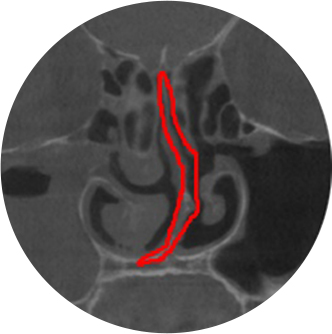

비중격만곡증, 비염, 축농증 소견

( 코 내부 CT촬영)

매부리코의 원인 중 코 내부구조가 변형된 경우 (위 CT사진 참고)

⇒ 비중격만곡증, 비염 , 축농증 동반 -